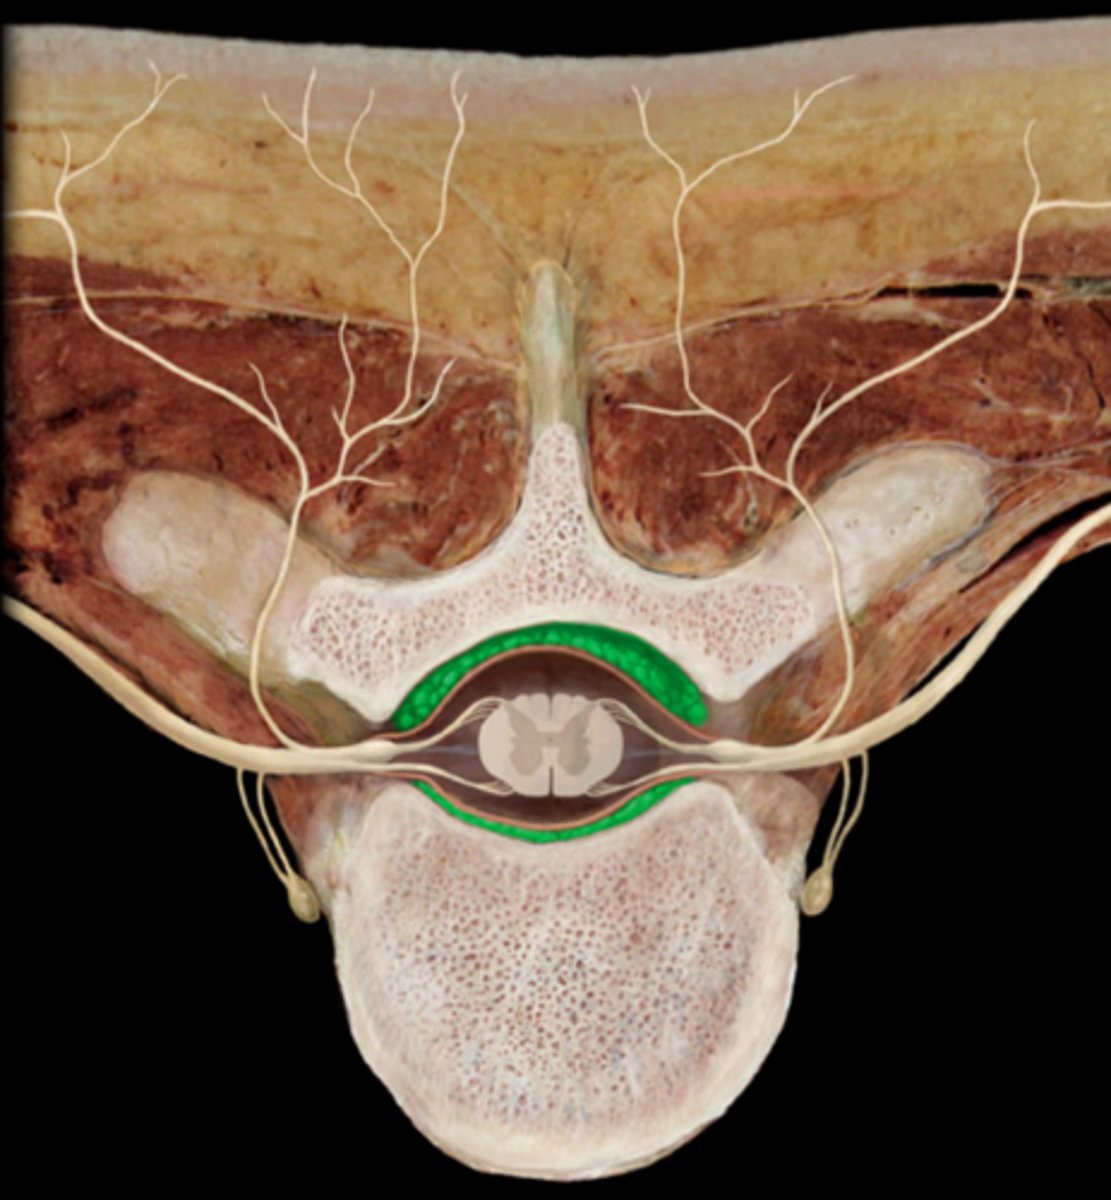

Conus Medullaris

Structure

Ventral rootlets

Dorsal rootlets

Ventral roots

Dorsal roots

Spinal ganglion

Spinal nerve

Ventral ramus

Dorsal ramus

Structure. broken

Cauda equina

Structure. horse tail

Spinal pia mater

Covering. will tap on spinal cord

Spinal epidural space

Space. will stick probe up under vertebrae/ above dura mater

Spinal subdural space

Space. under dura mater